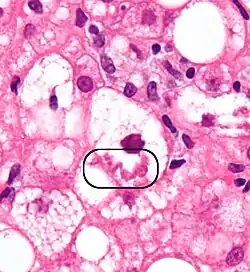

При окрашивании гематоксилином и эозином приобретают розовый цвет и хорошо различимы, однако, наилучший диагностический вариант — иммуногистохимическая окраска на убиквитин или цитокератины[1].

При микроскопии тельца Мэллори классифицируют следующим образом[1]:

- Тип I — параллельные филаменты;

- Тип II — беспорядочно ориентированные филаменты, встречающиеся по периферии клетки;

- Тип III — аморфные, располагаются вокруг центра клетки.